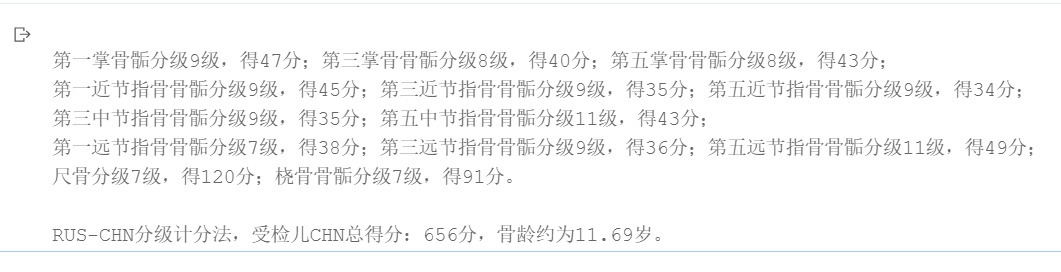

report = """

第一掌骨骺分级{}级,得{}分;第三掌骨骨骺分级{}级,得{}分;第五掌骨骨骺分级{}级,得{}分;

第一近节指骨骨骺分级{}级,得{}分;第三近节指骨骨骺分级{}级,得{}分;第五近节指骨骨骺分级{}级,得{}分;

第三中节指骨骨骺分级{}级,得{}分;第五中节指骨骨骺分级{}级,得{}分;

第一远节指骨骨骺分级{}级,得{}分;第三远节指骨骨骺分级{}级,得{}分;第五远节指骨骨骺分级{}级,得{}分;

尺骨分级{}级,得{}分;桡骨骨骺分级{}级,得{}分。

RUS-CHN分级计分法,受检儿CHN总得分:{}分,骨龄约为{}岁。""".format(

results['MCPFirst']+1,SCORE[sex]['MCPFirst'][results['MCPFirst']],\

results['MCPThird']+1,SCORE[sex]['MCPThird'][results['MCPThird']],\

results['MCPFifth']+1,SCORE[sex]['MCPFifth'][results['MCPFifth']],\

results['PIPFirst']+1,SCORE[sex]['PIPFirst'][results['PIPFirst']],\

results['PIPThird']+1,SCORE[sex]['PIPThird'][results['PIPThird']],\

results['PIPFifth']+1,SCORE[sex]['PIPFifth'][results['PIPFifth']],\

results['MIPThird']+1,SCORE[sex]['MIPThird'][results['MIPThird']],\

results['MIPFifth']+1,SCORE[sex]['MIPFifth'][results['MIPFifth']],\

results['DIPFirst']+1,SCORE[sex]['DIPFirst'][results['DIPFirst']],\

results['DIPThird']+1,SCORE[sex]['DIPThird'][results['DIPThird']],\

results['DIPFifth']+1,SCORE[sex]['DIPFifth'][results['DIPFifth']],\

results['Ulna']+1,SCORE[sex]['Ulna'][results['Ulna']],\

results['Radius']+1,SCORE[sex]['Radius'][results['Radius']],\

score,boneAge)

print(report)